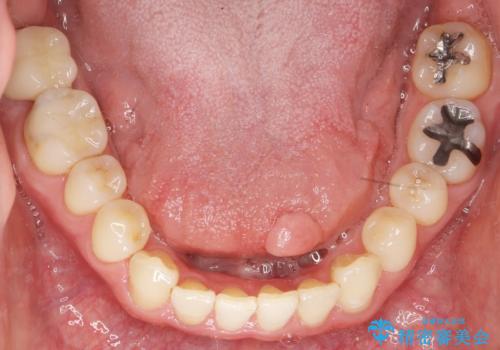

歯周外科処置(右下7遠心の骨整形及びディスタルウェッジ)により、深部に及ぶう蝕を除去するとともに歯肉縁上の健全歯質を獲得でき、適合の良い被せ物を作製することができました。

被せ物の種類:右下6 e-max press セラミックインレー

右下7 メタルボンドクラウン エコノミー